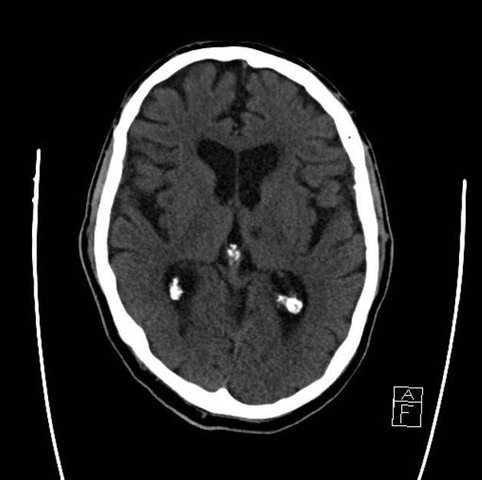

• Tomografía

Tomografía

Aportada por el paciente. refiere 5 meses de antigüedad